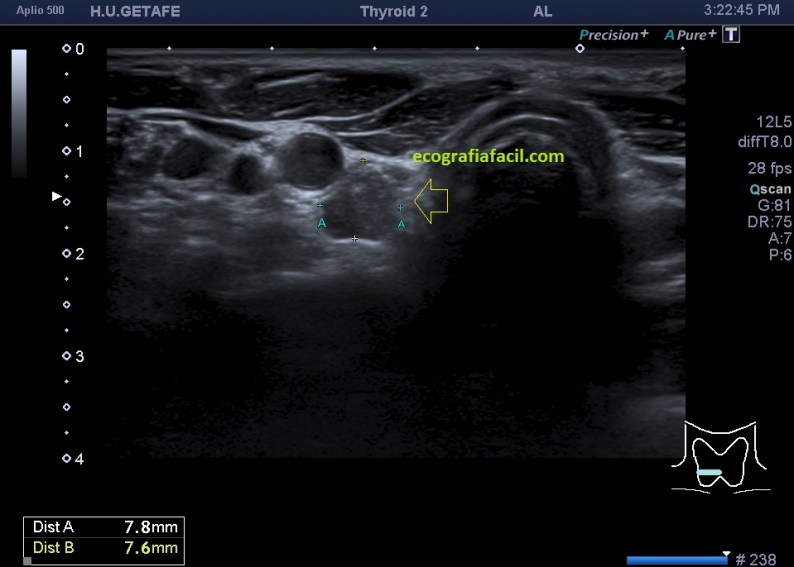

Cuando realizamos este estudio, lo hacemos a modo de control según protocolos de los especialistas de endocrinología ya sea por simple control o por sospecha de recidivas en sus despitajes con analíticas y otras pruebas. Me quiero parar en este último punto, ya que hoy lo que hoy quiero mostrarte el caso de una mujer que ronda los 40 años y a la que le vi esto en la eco tiroidea solicitada por su especialista, mira (flecha amarilla):

La flecha amarilla señala un hallazgo anormal, una vez localizado, protocolo habitual con medidas, doppler, zoom si fuera necesario, documentando bien todo.

Una vez conocida la normalidad relativa de esta arquitectura anatómica volvemos al hallazgo, que como puedes comprobar tiene aspecto nodular, hipoecogénico, de bordes mal definidos y eventualmente, como es el caso de la imagen siguiente (corte longitudinal), tiene microcalcificaciones, semiología ésta de altísimo grado de sospecha.